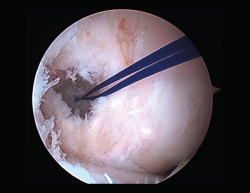

Un diagnóstico y una planificación correctos son fundamentales. En caso de rotura de plastia del LCA (Figura 3), se hace obligatoria, además de una detallada exploración, un correcto estudio radiológico completo que incluya radiología convencional y resonancia magnética (RM) –estudio de lesiones acompañantes o degeneración previa–. En ocasiones en donde la anamnesis/exploración lo justifique, pueden ser también necesarias telemetrías de extremidades inferiores, radiología forzadas (si existiera inestabilidad mediolateral) o tomografía axial computarizada (TAC) –valoración de la posición y la calidad de los túneles–.

Figura 3. Rotura de la plastia del ligamento cruzado anterior.